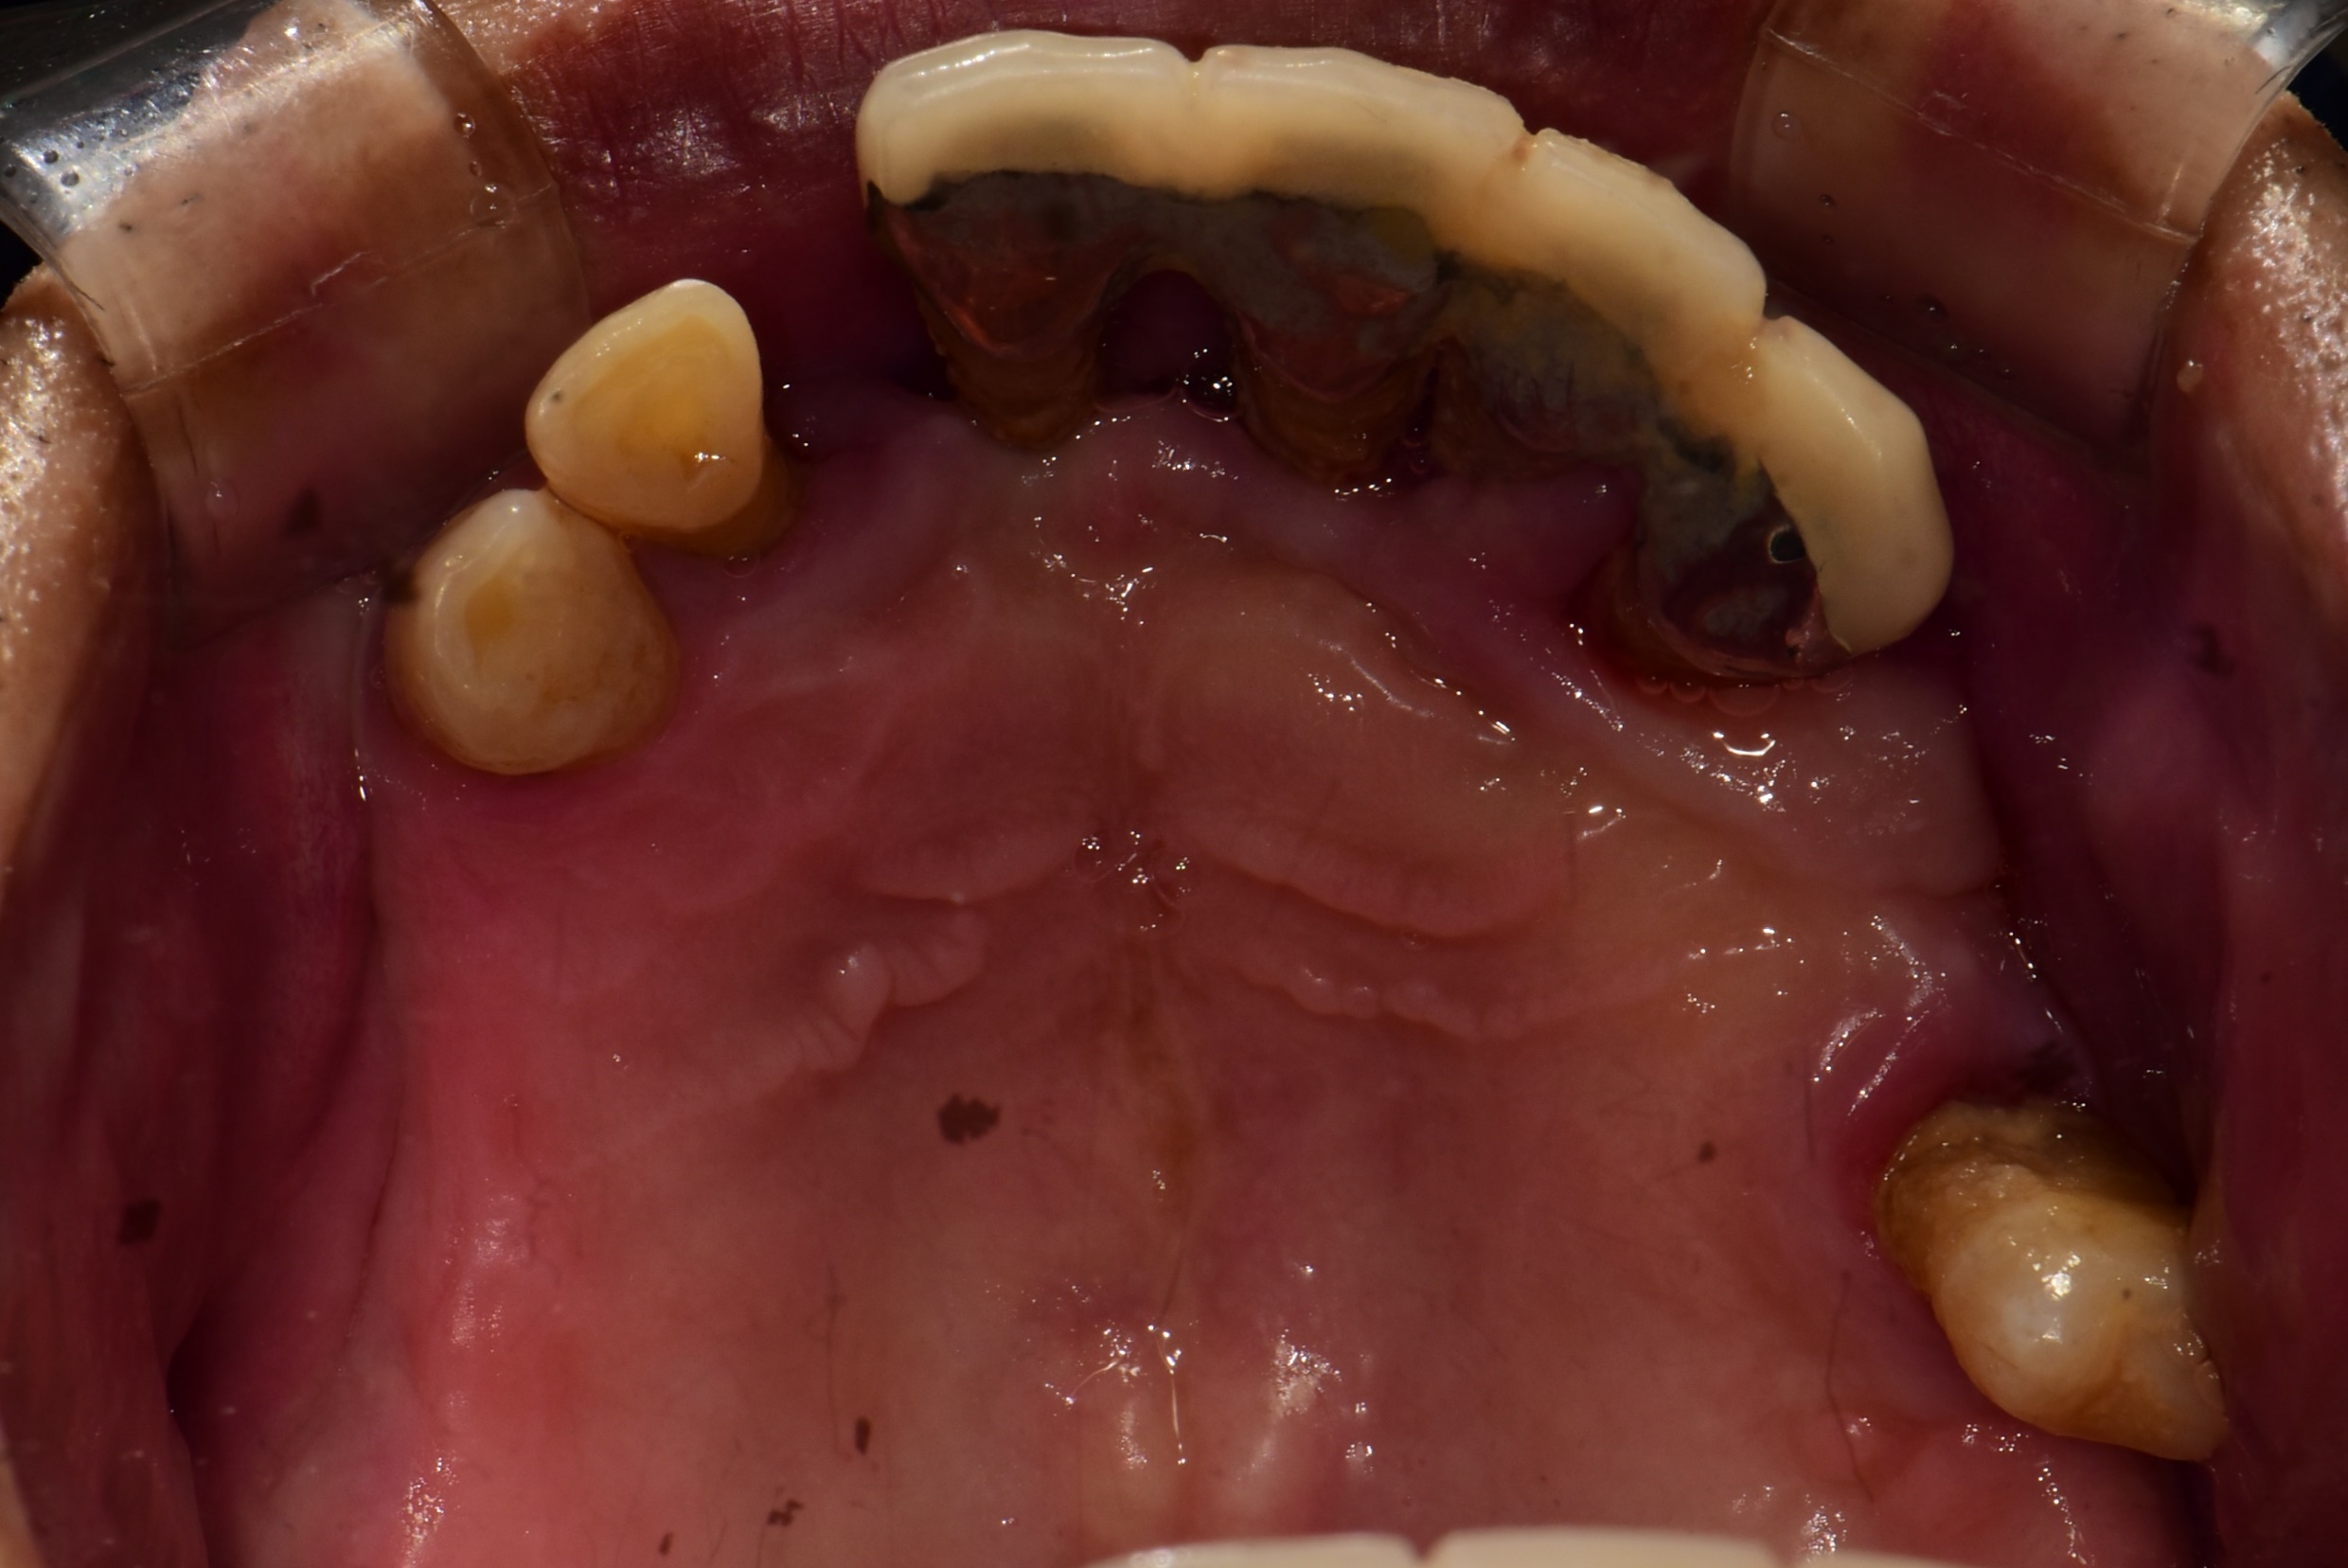

오랜기간 어금니가 없이 지내셨던 60대 남성분의 치료 사례입니다.

처음 김포 치과에 내원하셨을 당시 위에는 송곳니 하나를 제외하고는 다 흔들리고 어금니는 빠진지 오랜된 상태였습니다.

<치료 전>